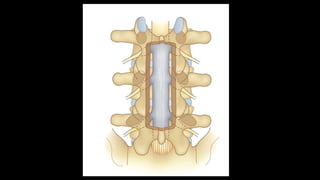

Current trends

• Use Interspinous Process spacers

• Principle – they are inserted into interspinous space and used to distract

adjacent interspinous processes, thus increasing spinal canal and foraminal

capacity.

• The patient likely to benefit is one who has neurologic claudication that is

relieved within 5 minutes of sitting down, and no more than grade I

spondylolisthesis

• It should not be used in poor bone due to risk of fractures

• Wu et al (2014) & Hong et al (2015) in their metanalyses compared ISP and

open decompression – outcomes were similar, but the ISP group had

significantly higher reoperation rates